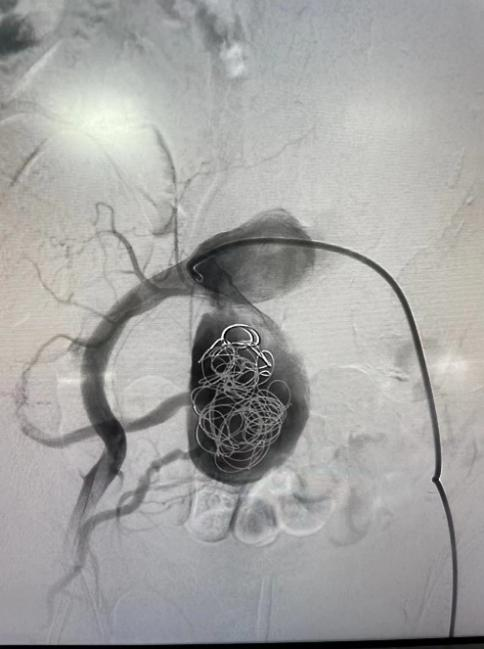

右側(cè)髂動(dòng)脈動(dòng)脈瘤栓塞術(shù)

據(jù)了解,2月24日,患者李伯在進(jìn)行腦血管造影檢查時(shí),意外發(fā)現(xiàn)了腹主動(dòng)脈有巨大的動(dòng)脈瘤及雙側(cè)髂動(dòng)脈巨大動(dòng)脈瘤。經(jīng)過(guò)測(cè)量,李伯腹主動(dòng)脈夾層動(dòng)脈瘤瘤體直徑約8.6cm,上下徑約11.6cm,瘤體較大且延伸至雙側(cè)髂動(dòng)脈。

2月28日,神經(jīng)內(nèi)科介入團(tuán)隊(duì)在西安交通大學(xué)第一附屬醫(yī)院血管外科蔡惠副主任的指導(dǎo)下成功為李伯實(shí)施了“右側(cè)髂動(dòng)脈瘤栓塞+腹主動(dòng)脈瘤腔內(nèi)隔絕術(shù)”,手術(shù)歷時(shí)2小時(shí)順利完成。

術(shù)后,李伯再次造影提示支架貼合良好,且未發(fā)現(xiàn)內(nèi)漏、周?chē)K器血管閉塞等并發(fā)癥。次日李伯就能下床活動(dòng),行走自如。目前,西電集團(tuán)醫(yī)院神經(jīng)內(nèi)科介入團(tuán)隊(duì)已成功為四名患者“拆除”腹腔“炸彈”。